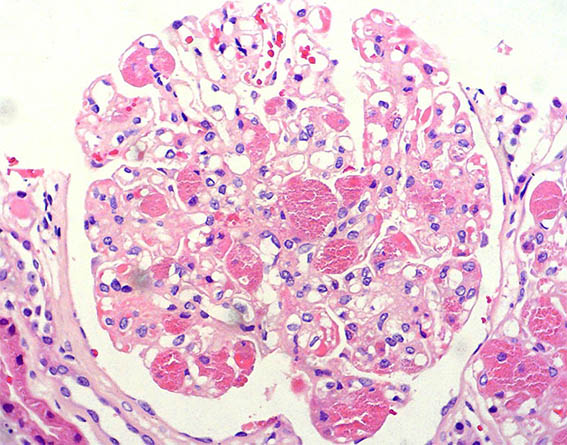

Se hace biopsia renal, observe las imágenes.

Figura 2. H&E, X400.